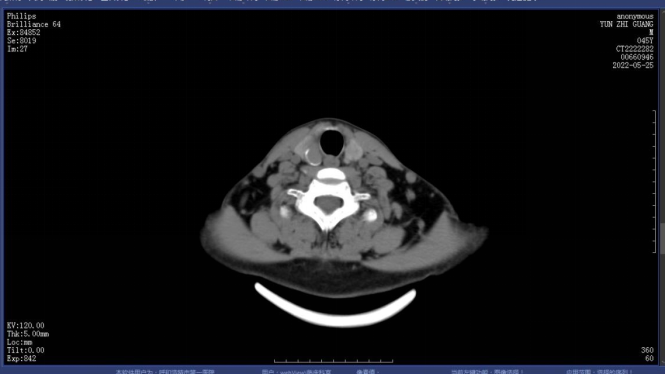

图4.1.术前甲状旁腺CT定位

图4.2.术前甲状旁腺CT定位